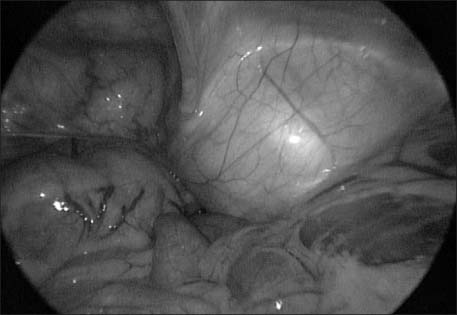

Fig. 2

Laparoscopic exploration showed well demarcated bulging mass from abdominal wall without connection of internal organ.

Fig. 2 Laparoscopic exploration showed well demarcated bulging mass from abdominal wall without connection of internal organ.